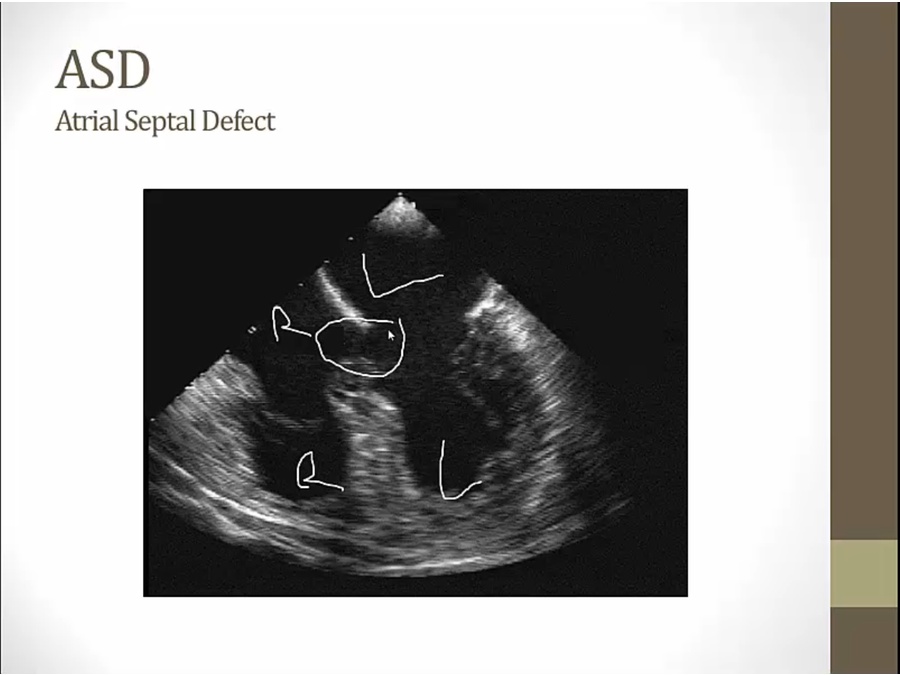

ASD

major consequence: add volume to right side of heart

increased flow across PV/TV causes systolic ejection murmur

Secundum

located in middle of wall: mid septum

Primum

left: septum primum fusion with EDC

right: non fusion, ASD

seen in endocardial cushion defects, collective defects in down syndrome

hole located lower

echo: RA on left, LA on right